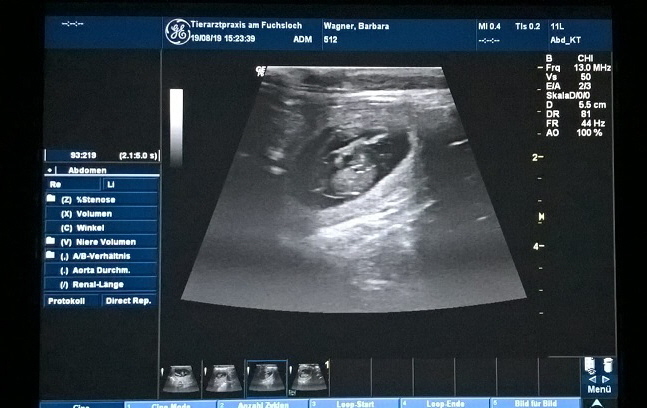

Unser Mädel ist schwanger !!!

ich war beim Ultraschall mit Vicky, und dort konnte meine Tierärztin auf jeden Fall, mal 3 Welpen erkennen.

Jetzt sind es noch 3 Wochen bis zur Geburt.

Vicky ist ständig hungrig und auch schon ganz schön proper mittlerweile

nun hoffen wir das weiterhin alles gut läuft und wir bis um den 20.09.2019 kleine Welpen bekommen